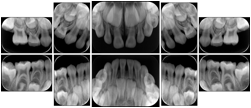

- OO-1. Intra-oral Full Mouth Series Structured Display